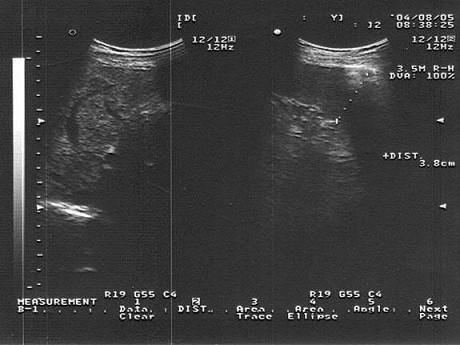

问题 男,48岁,上腹胀痛,纳差,血吸虫病多年。结合超声声像图,诊断为?(?)

选项 A.血吸虫肝纤维化 B.脂肪肝 C.细菌性肝脓疡 D.肝豆状核变性 E.肝炎

答案 A